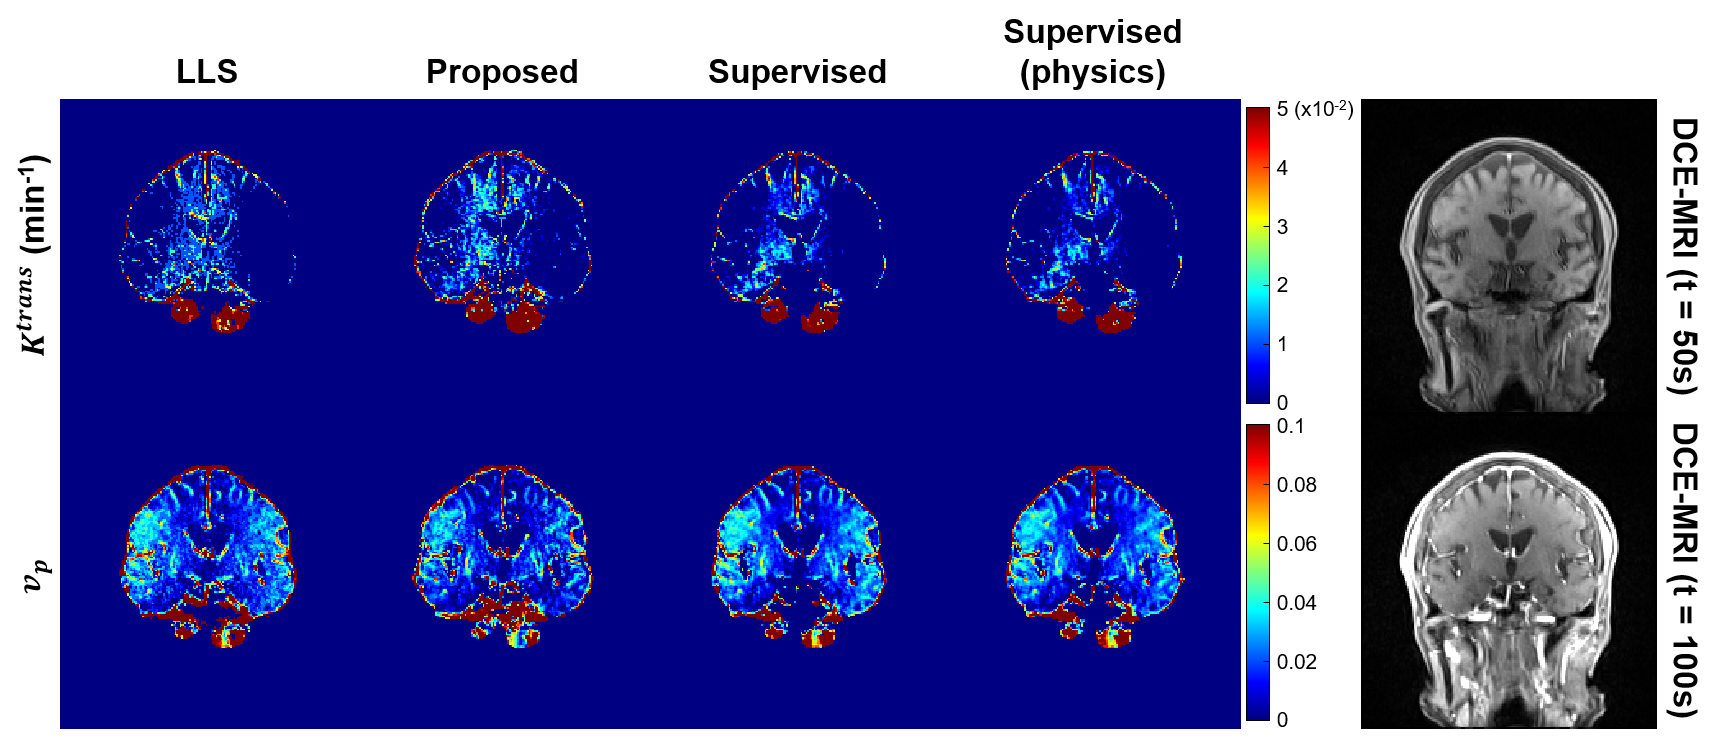

Additionally, Fig. 7 shows the reliable results obtained by our CycleGAN when applied to the Patlak model. This underscores the versatility and effectiveness of our approach beyond specific model applications.

In summary, we have proposed a novel unpaired deep learning method, based on physics-driven CycleGAN, for pharmacokinetic estimation. Our findings demonstrate that the proposed CycleGAN method accurately captures tumor characteristics and provides estimation results comparable to the LLS method while reducing computational complexity. However, supervised learning methods, even when incorporating the physics model, tend to yield exaggerated values for and and exhibit limitations in accurately estimating in the tumor region. Furthermore, our CycleGAN approach shows consistent and reliable results when applied to the Patlak model. These results highlight the robustness and applicability of our CycleGAN method for accurate pharmacokinetic parameter estimation.